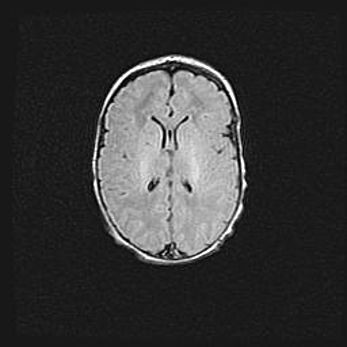

Сообщающаяся гидроцефалия. Кистозная энцефаломаляция головного мозга.

Возраст: 3 месяца 4 дня

Вес: 3100 г

Пол: женский

Окружность головы: 34 см

Срок гестации: 31 неделя

Кистозная энцефаломаляция головного мозга - одна из форм поражения головного мозга в детском возрасте. Характеризуется возникновением множественных и распространённых кист в коре, белом веществе и подкорковых образованиях головного мозга у плодов, новорождённых и детей раннего возраста. Развитие кистозной энцефаломаляции связано с внутриутробной асфиксией и гипотонией, родовой травмой, тромбозом синусов, пороками развития сосудов, инфекциями, сепсисом и другими причинами. Наиболее значимые инфекционные агенты: вирусы простого герпеса, цитомегалии, краснухи, токсоплазмы, энтеробактерии, золотистый стафилококк и другие.